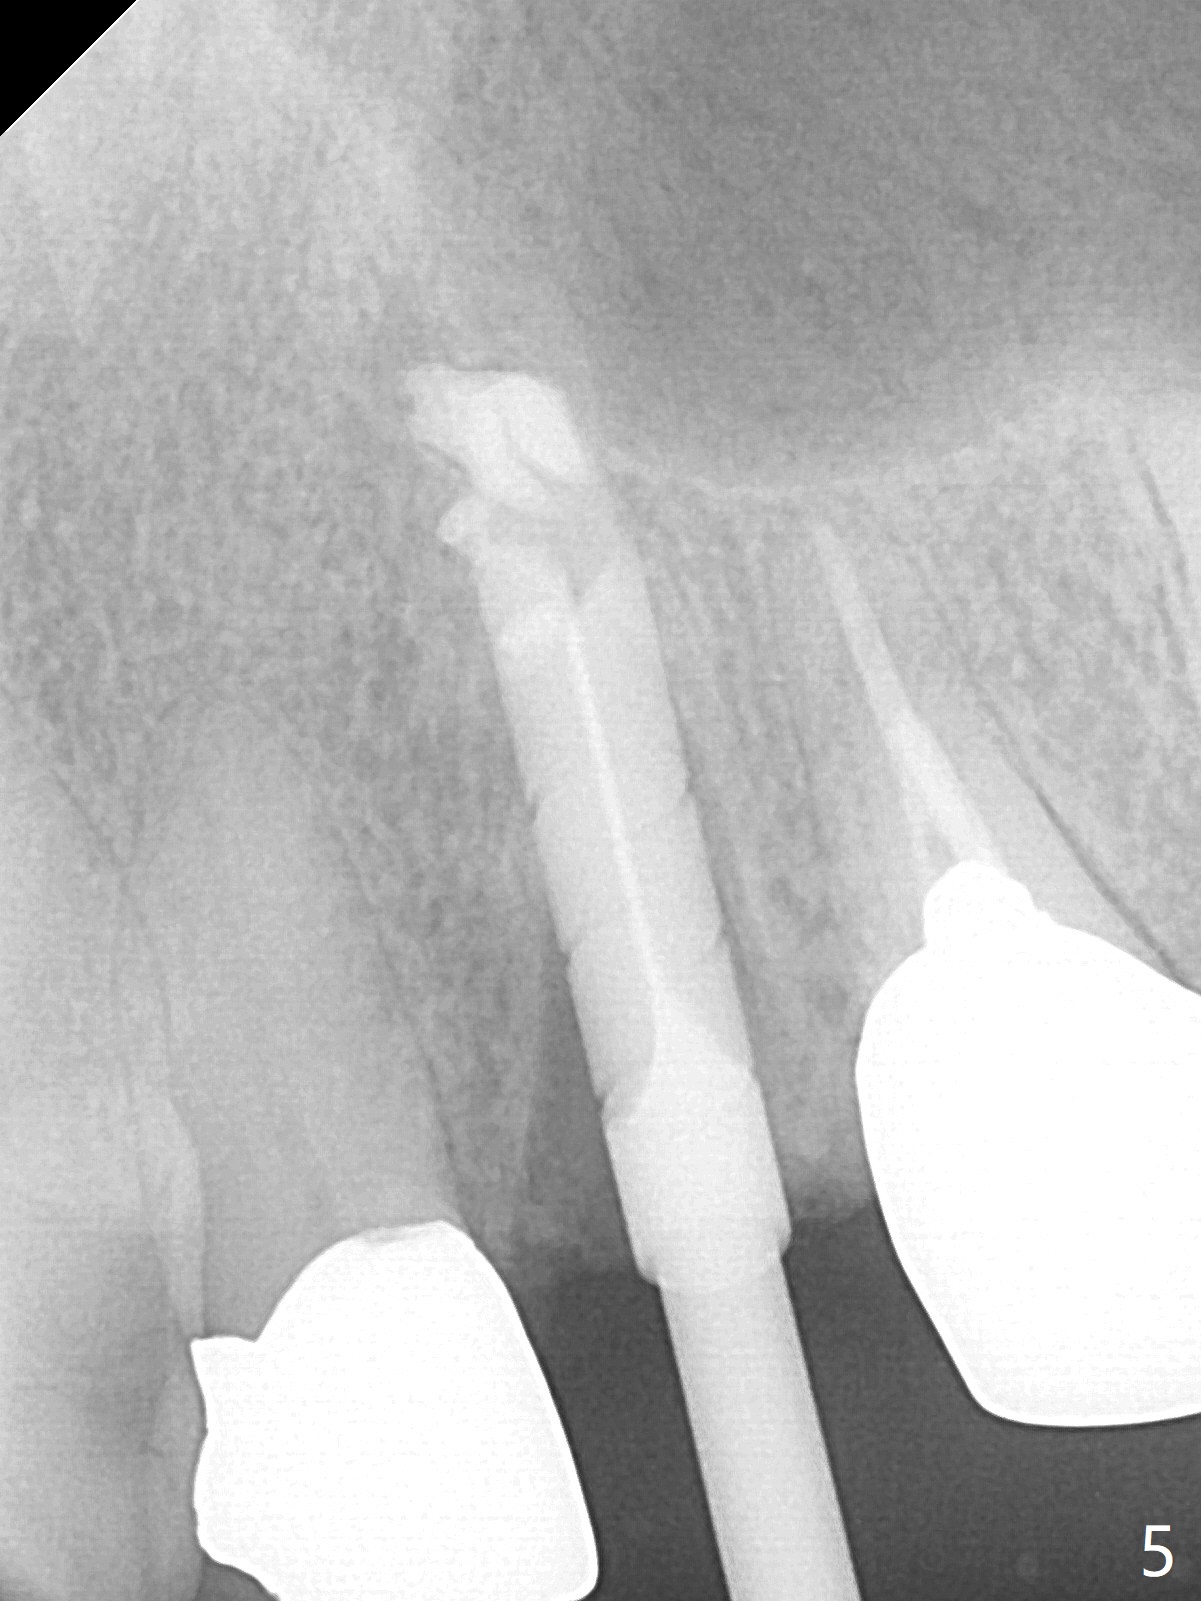

Extraction of the residual root at #11 (Fig.1) turns out to be difficult (Fig.2 (arrow: after use of small elevator). The tooth is sectioned (Fig.2 *); the palatal portion is removed, while the buccal one is trimmed until new moon-shaped and subgingival (Fig.3 * (gauze (G) packed in the socket while photo taking)). Initial osteotomy is 20 mm deep with nasal floor perforation (Fig.4). The subsequent depth is 17 mm (Fig.5). When a 5x17 mm tissue-level implant is placed (Fig.6,7; >60 Ncm), there is a gap between it and the socket shield (Fig.6 *). Gap-filling Vera Graft (Fig.8 *) also covers the shield prior to fabrication of an immediate provisional (Fig.9). There is no apparent bone loss 3.5 months postop (Fig.10). There is no buccal plate resorption 9 months postop (Fig.11). The implant is doing well 2 years postop (1 year 9 months post cementation, Fig.12).